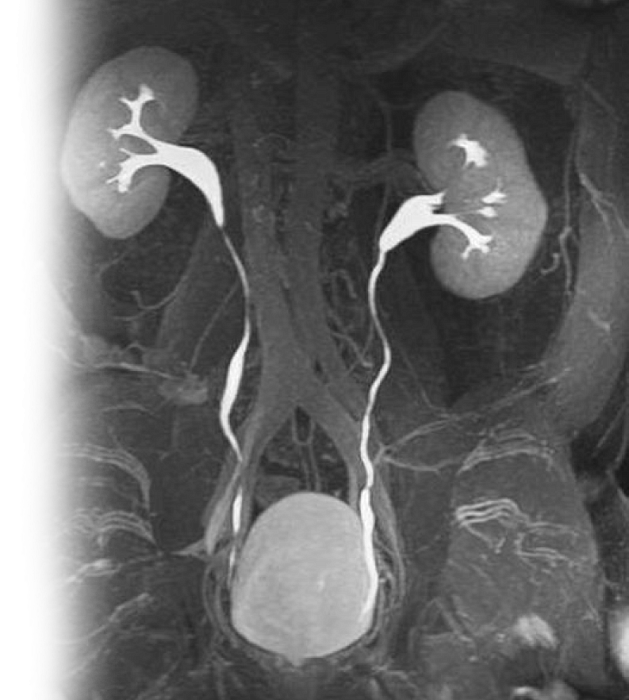

МР контрастная урография

МР контрастная урография – важный метод исследования с применением контрастирующего вещества, который позволяет визуализировать лоханки и мочеточники, паренхимы почек и окружающих мягких тканей.